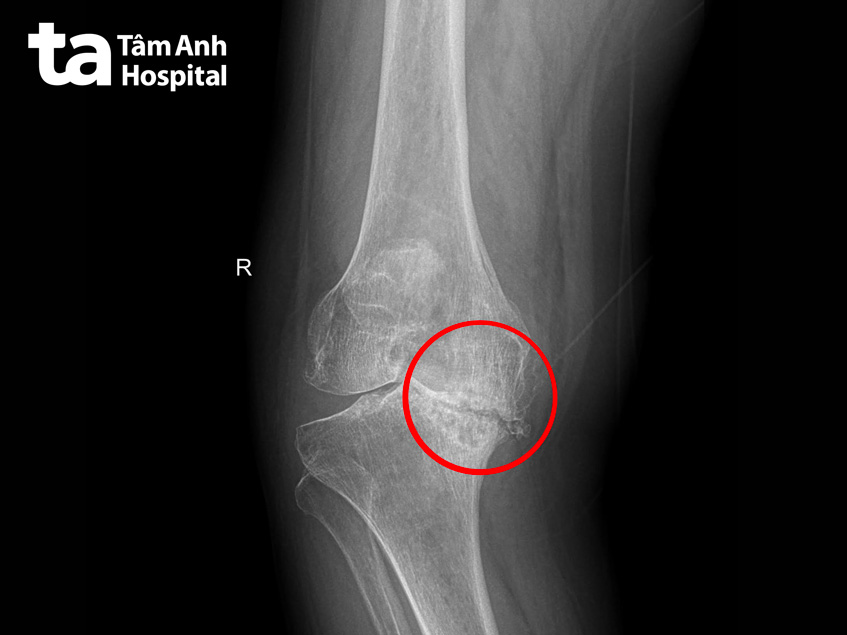

Ngày 18/6, ThS.BS.CKI Đào Duy An Duy, Trung tâm Chấn thương Chỉnh hình, Bệnh viện Đa khoa Tâm Anh TP HCM, cho biết người bệnh bị thoái hóa khớp gối giai đoạn cuối ở cả hai chân. Lớp sụn khớp nằm giữa xương đùi và xương chày tiêu biến, các đầu xương ma sát vào nhau khi người bệnh di chuyển.

Tình trạng này xảy ra trong một thời gian dài, xương đùi không ngừng tì đè, tạo thành lỗ khuyết lõm ở xương chày. Hậu quả là dây chằng bên trong bị co rút, dây chằng bên ngoài bị giãn nhiều. Tất cả những yếu tố này làm cho hai chân của bà Vững bị cong vẹo bất thường.